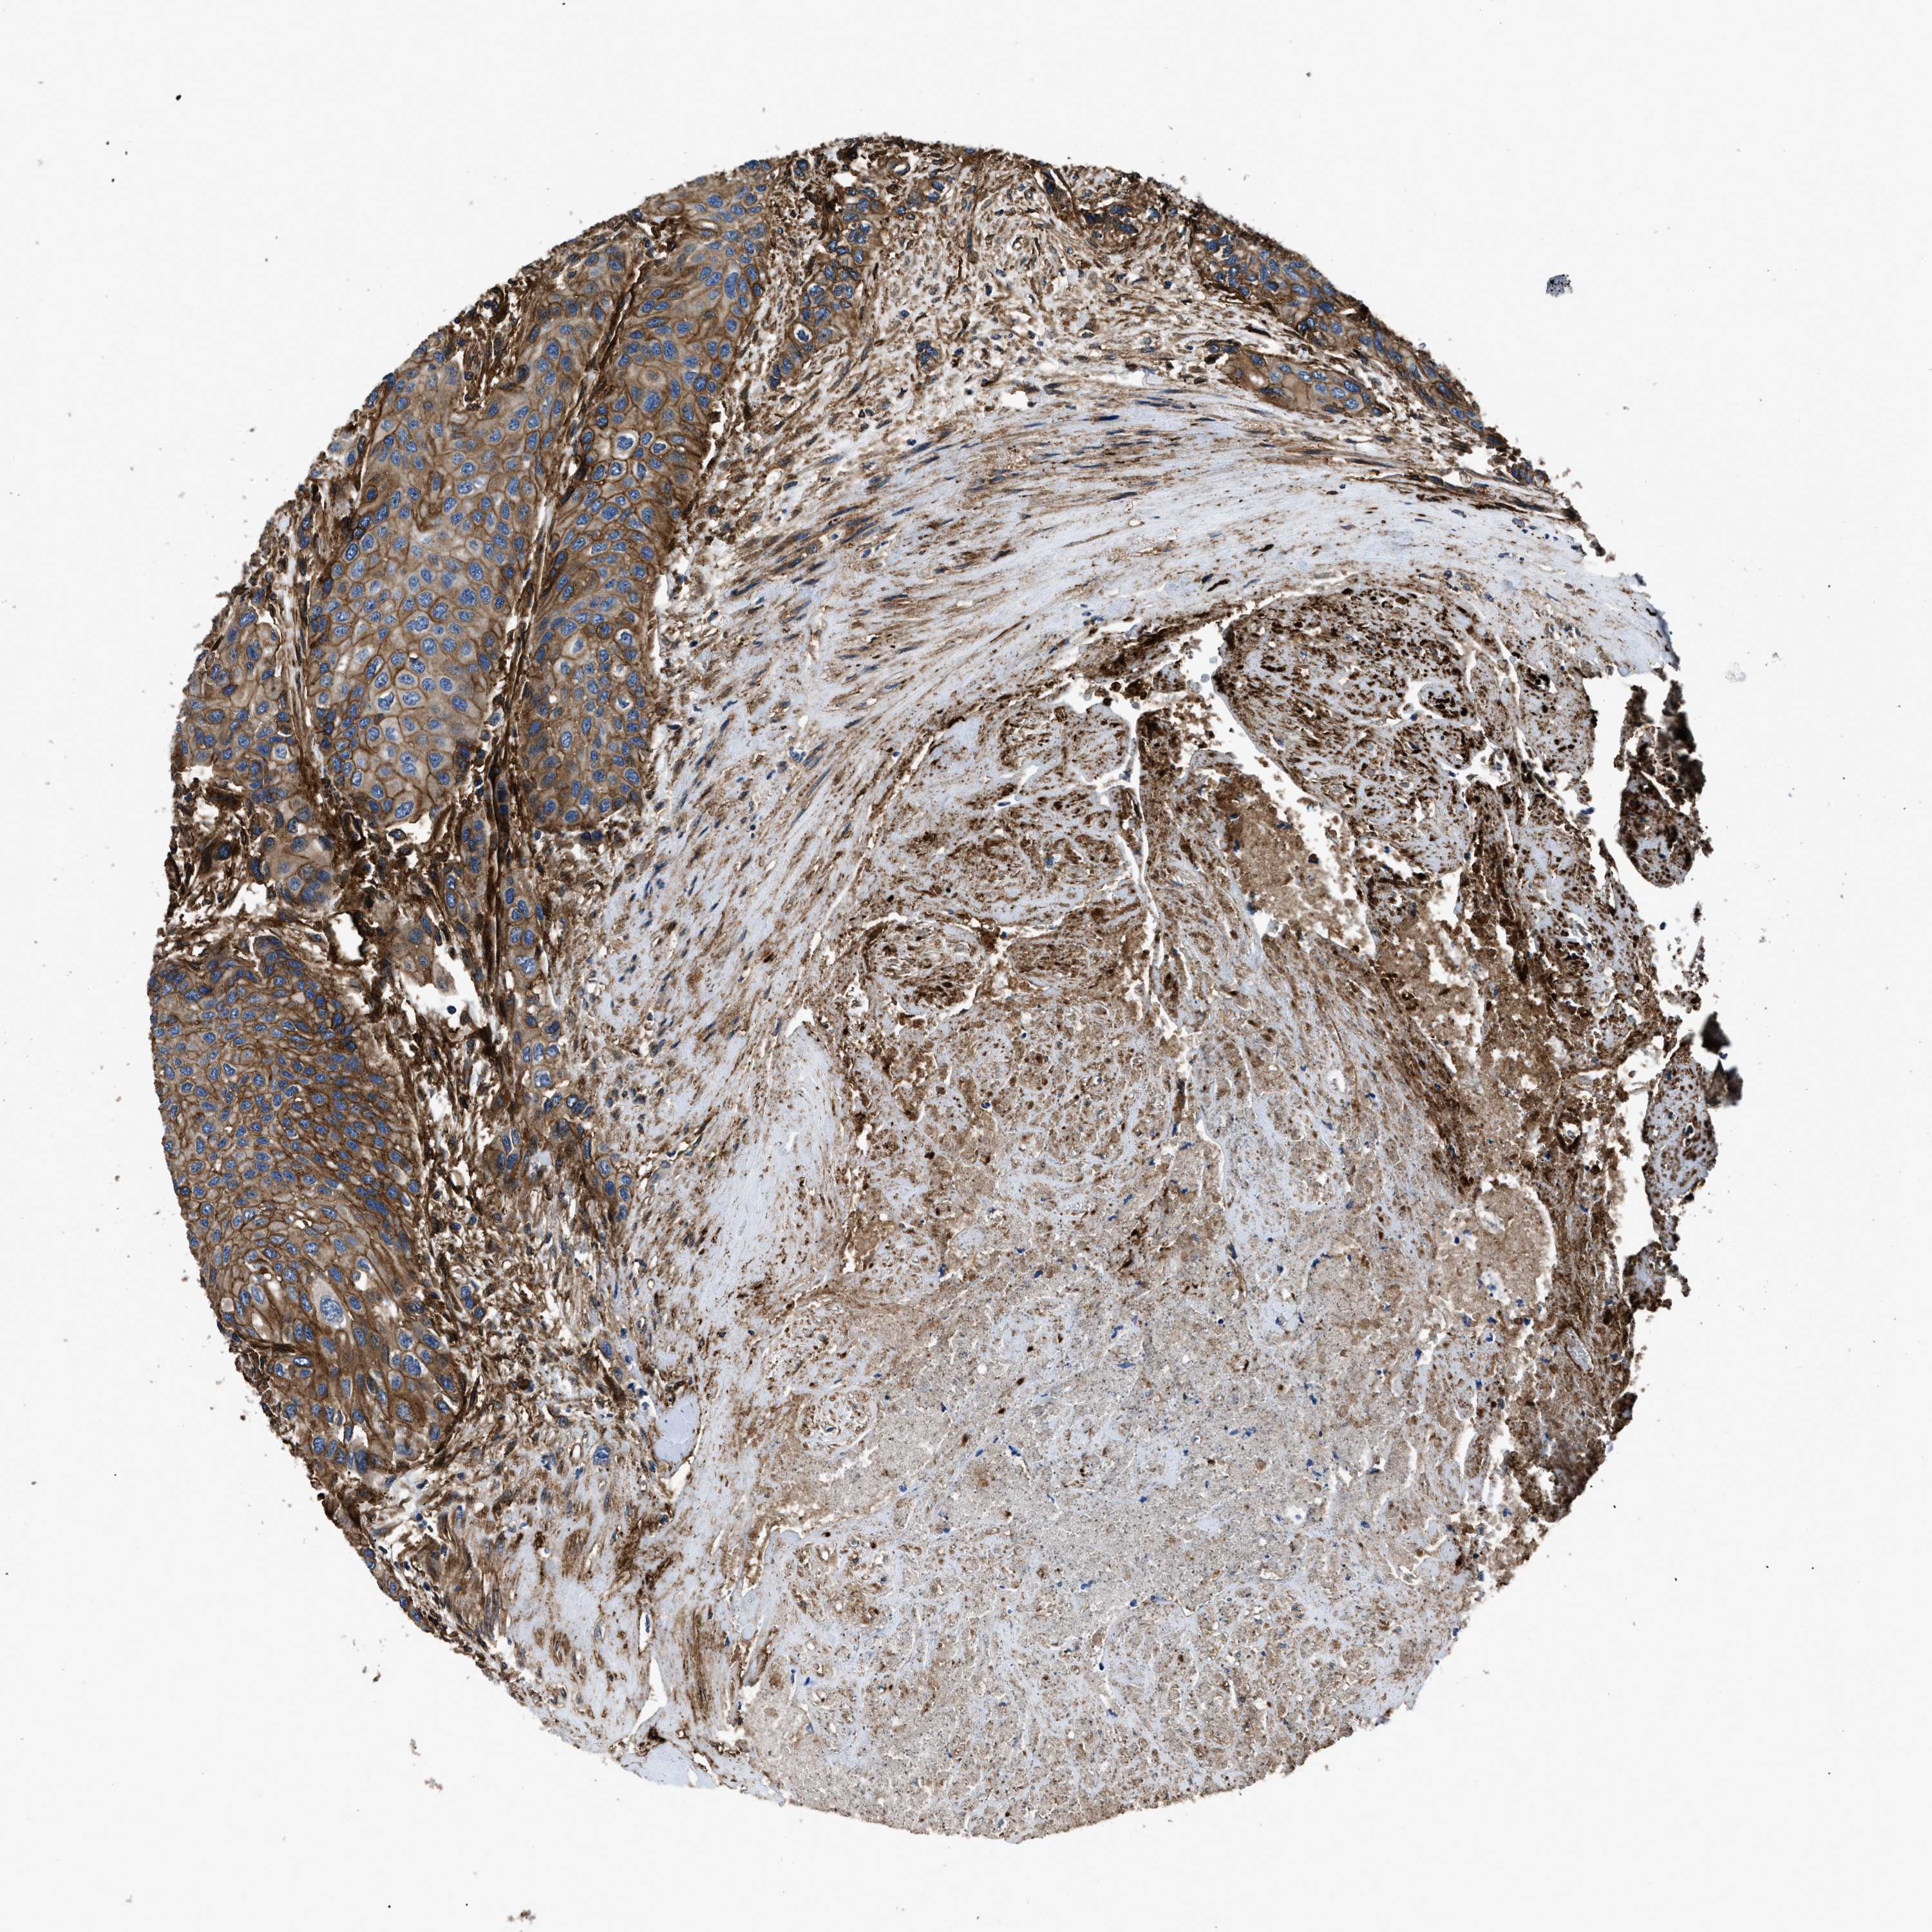

UROTHELIAL CANCER - Protein expressioni

A mouse-over function shows sample information and annotation data. Click on an image to view it in a full screen mode. Samples can be filtered based on level of antibody staining by selecting one or several of the following categories: high, medium, low and not detected. The assay and annotation is described here.

Note that samples used for immunohistochemistry by the Human Protein Atlas do not correspond to samples in the TCGA dataset.

Antibody stainingi

Antibody staining in the annotated cell types in the current human tissue is reported as not detected, low, medium, or high, based on conventional immunohistochemistry profiling in selected tissues. This score is based on the combination of the staining intensity and fraction of stained cells.

Each image is clickable and will lead to virtual microscopy that enables deeper exploration of all samples and also displays staining intensity scores, fraction scores and subcellular localization as well as patient and tissue information for each sample.

Antibody HPA009285

Antibody HPA017139

Antibody CAB017826

Urothelial carcinoma, Low grade

Urothelial carcinoma, High grade